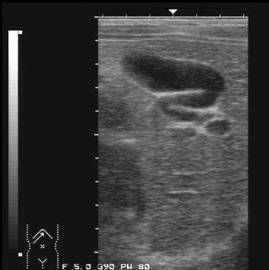

Hidrops vezicular

Colecistita acuta reprezinta o cauza frecventa de crestere a volumului vezicular, care constituie, uneori, singurul argument ecografic prin care se poate sustine diagnosticul.

Colecistita acuta. Colecit acalculos dilatat cu ingrosarea peretilor si sludge